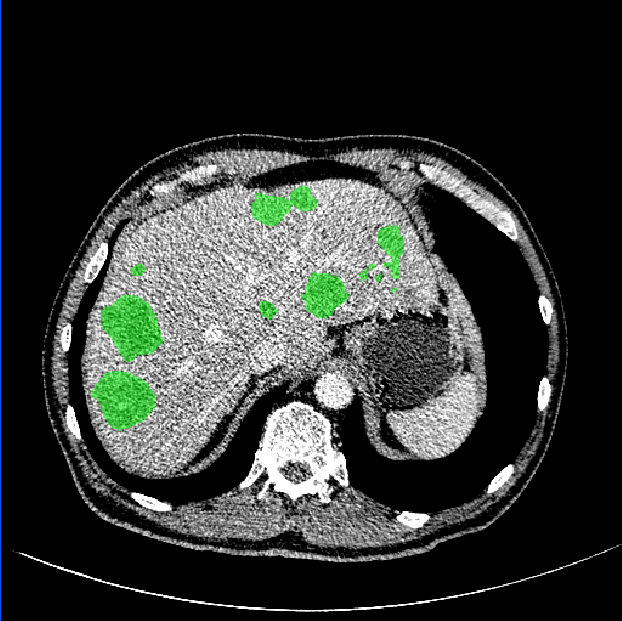

As shown in Fig. 3, our method demonstrates superior qualitative results, especially in the notoriously small tumors segmentation. In Table 1, the results show that the M-Net with the LR-Net achieves better performance than M-Net alone on all the evaluation criteria. This indicates indicates the significance of LR-Net on accuracy improvement. Then, we evaluate the performance of MapDice loss. By comparing the results with and without the MapDice loss, it is apparent that MapDice loss contributes a lot for segmentation accuracy improvement. In particular, the MapDice loss yields the superior results of NI-DM regression, while Dice loss shows a significant drop in the last four columns of Table 1. This indicates that distance map can help the network to capture semantically meaningful regions and produce more accurate reslults. The constant value , used to balance the magnitude difference of two different losses, is also verified to be effective for the performance improvement.